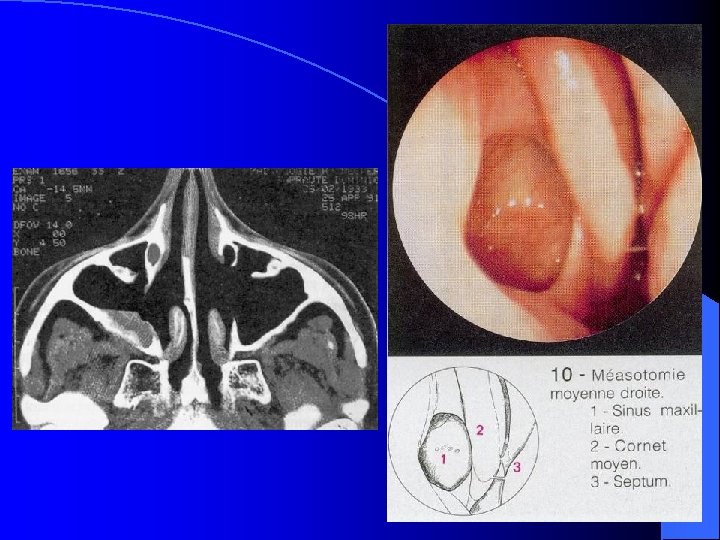

MALADIES INFECTIEUSES RHINO SINUSIENNES SINUSITE MAXILLAIRE CHRONIQUE TRAITEMENT Prise en charge Médico-Chirurgicale • Lavage des fosses nasales • Vaso-constricteurs locaux • ATB probabiliste orale 21 jours • Méatotomie moyenne endonasale • Voie vestibulaire type Caldwell-Luc Objectif: • Levée de l’obstacle ostial • Prélèvements bactério et anapath (Dc différentiel) • Suppression du foyer infectieux (truffe aspergillaire, foyer dentaire)

MALADIES INFECTIEUSES RHINO SINUSIENNES SINUSITE MAXILLAIRE CHRONIQUE FORMES CLINIQUES SMC Aspergillaire: • ATCD de soins dentaires maxillaires • RX, TDM: Micro-opacité de tonalité métallique au sein d’une opacité complète du sinus maxillaire • Prise en charge chirurgicale : Méatotomie moyenne endonasale pour détersion du sinus maxillaire et exérèse de la truffe aspergillaire Voie vestibulaire type Caldwell-Luc • Aucune indication à un traitement médical antimycosique SMC de l’enfant: (rare) Contexte de pathologie générale à recher Mucoviscidose, Dysfonction ciliaire (Kartagener)